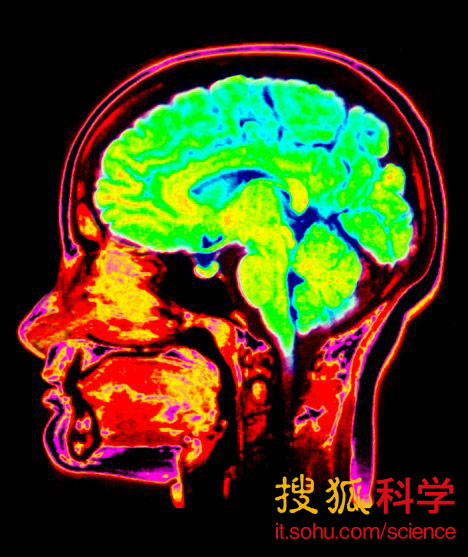

帝摩斯在试验中使用了磁共振成像(MRI)对885名实验者的大脑进行了扫描,这些实验者的平均年龄在3岁到20岁之间。结果,科学家通过大脑扫描识别出了231个大脑骨骼生物标记物,在进行结合之后,科学家惊诧的发现,这些骨骼生物标记物可以判断出人们的真实年龄,准确度高达92%。